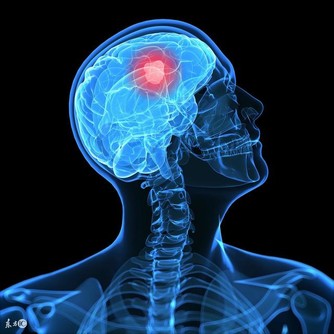

癌症是人人聞之色變的一種疾病,有很多種癌症至今都沒有治癒的方法。癌症也被稱為「絕症」,只要聽說某個人罹患癌症,基本就是下了死亡判決書。癌症有一個特點大家必須要知道,就是35℃下是癌細胞最喜歡的溫度,也是令它們最活躍的溫度。 一旦身體溫度高於39.6℃,癌細胞就會死亡! ▼過去患癌症的人遠不如現在多,大部分現代人由於壓力過大和飲食不當等原因,正常體溫都在35℃-36℃,而這種「低體溫狀態」正是高血壓、高脂血症、糖尿病、肥胖、更年期障礙、憂鬱症、心肌梗塞、癌症等疑難雜症高發的重要原因。總而言之,體溫是決定生老病死的關鍵。

既然低體溫容易罹患癌症,那麼高溫是不是可以殺滅癌細胞呢?答案是這絕對是可以的!這不是開玩笑,熱療已經成為對付腫瘤的一種新方法,國外醫學家甚至將它稱作「醫療春天的到來」。 從世界範圍來看,被稱為「醫學之父」的古希臘名醫Hippocrates也曾用加熱法來治療腫瘤。一百多年前,德國醫生Coley發表了有關「發熱療法」的研究,往患者體內注射「Coley毒素」誘發患者發熱,他用這種方法治療了38例晚期癌症。癌症細胞比正常的人體細胞更為「怕熱」,所以,在同樣的加熱溫度下,癌細胞熱得停止生長,正常的組織細胞卻依然可以「悠哉游哉」。這樣一來,既能殺滅腫瘤組織,又可以最大限度避免「誤傷」正常組織。 有人也曾經試過把自己架在火上烤,希望藉此能殺滅體內的癌細胞,這就有點「病急亂投醫」了,因為人體的導熱性比較差,烤火或者蒸桑拿無法將熱量傳遞到腫瘤組織,所以起不到殺滅癌細胞的作用。如果將身體長時間暴露在高溫之下,可能會導致身體組織脫水和灼傷,這是得不償失的一種做法。 而且熱療對實體腫瘤效果比較明顯,而對於白血病幾乎沒什麼效果,因為白血病的病源在骨髓中,我們目前的醫學是無法讓高溫進入全身骨髓的。所以與其等患了癌症再去找方法,不如學會預防癌症。 既然我們知道低溫是癌細胞最喜歡的溫度,那就設法提升自身溫度,把癌細胞滋生的溫床徹底掀翻掉!醫學研究表明,體溫每升高1℃,人體免疫力就會提高30%;相反,體溫降低,免疫力就會下降。 怎樣提高基礎體溫呢?試試下面的方法吧。 1. 每天喝五杯白開水,持之以恆。 2. 少淋浴,多泡熱水澡,使血液循環更暢通,保持?的活性。 3. 增加體力勞動,至少在家做家務少用吸塵器、洗衣機之類的,親自動手吧。 4. 夏天少開冷氣。 5. 不要過分減少鹽分的攝入。 6. 不要過度飲食,少吃冰冷的食物。 其中最重要的就是第一點,現在很多人都用純凈水來代替白開水,這並不是一種健康的習慣。如今日本很流行白湯排毒法,也就是要把水煮沸,然後喝溫熱的白開水排毒!這種療法源自於印度的阿育吠陀(Aayurveda) ,只要身體熱起來就能達到和用芝麻油按摩讓身體熱起來同樣的效果!,由於簡單又不必花錢,因此日本藝人千葉麗子推薦之後, 一群明星也效仿,成功造成一股風潮 煮開並沸騰3分鐘的開水,可以使水中的氯氣及壹些有害物質被蒸發掉,同時又能保持水中對人體必須的營養物質。堅持每天五杯白開水,不僅能提高基礎體溫,還有很多意想不到的效果喔! 1. 緩解便秘,多喝白開水可以促進胃腸蠕動,軟化大便。 2. 利尿,白開水有利尿的功效,可以使輸尿管、膀胱流暢,防止結石發生和細菌感染。 3. 幫助身體排毒,喝熱水時體溫上升,會使得毒素隨汗液一起排出體外。 4. 減少痛經,白開水的熱量對腹部肌肉有著鎮靜和舒緩的效果,能有效減少痛經。 5. 減肥,喝白開水能促進新陳代謝,有助於分解脂肪組織。 6. 緩解咳嗽和喉嚨痛,白開水是天然的感冒良藥,它的化痰效果使你的喉嚨不會有那麼重的異物感,而且喝幾口白開水,鼻子也很容易通氣。 喝白開水也不能盲目地硬灌,最好分時間段飲用,效果會倍增喔。 1. 早晨剛起床,此時正是血液缺水狀態。 2. 上午8時至10時左右,可補充工作時間流汗失去的水分。 3. 下午3時左右,正是休息的時刻。 4. 睡前,睡覺時血液的濃度會增高,如睡前適量飲水會沖淡積壓液,擴張血管,對身體有好處。 很多人往往在口渴時才想起喝水,而且往往是大口喝,這種做法也是不對的。喝水太快太急會無形中把很多空氣一起吞咽下去,容易引起打嗝或是腹脹,因此最好先將水含在口中,再緩緩喝下,尤其是腸胃虛弱的人,喝水更應該一口一口慢慢喝。 從今天開始記得要每天都喝溫熱開水,提早預防癌症!癌症是十分頑強的一種病症,千萬不要等到患病後才後悔為何沒有早預防。了解癌細胞的生存環境,知道它的弱點,將癌症扼殺在搖籃里。把這篇文章分享出去,讓大家都深入了解一下吧!